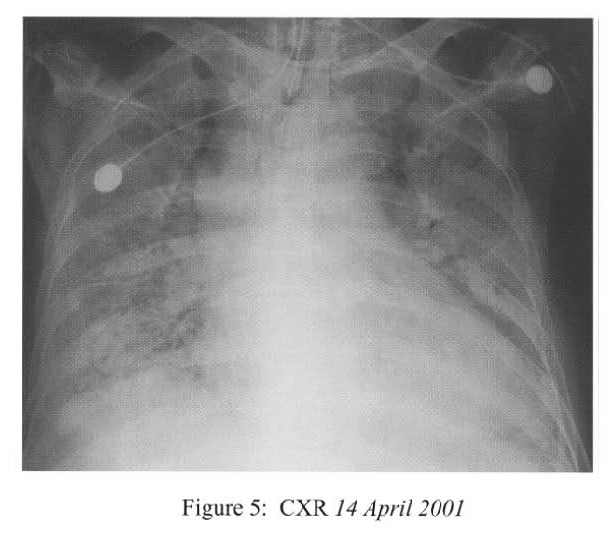

She deteriorated further on ih April 2001 with desaturation despite high flow oxygen. lCU admission was sought but there was no bed available. She was intubated and mechanically ventilated under sedation (midazolam infusion). CXR showed rapid deterioration to bilateral diffuse dense consolidation (Figure 3).

Radiological features are also diverse and variable 15,16.On the chest radiograph, early signs include miliary shadows, diffuse reticular interstitial opacities, patchy alveolar opacities, segmental or lobar opacities. In the advanced stage, there can be extensive airspace shadows affecting both lungs, with occasional pleural or pericardial effusion. Without treatment, ARDS quickly evolves. Rarely, ARDS develops after antihelminthic treatment due to release of toxic breakdown products 17.On the abdominal radiograph, there can be thickened mucosal folds, segmental small bowel dilatation or perforation. Among all these variable radiological features, a characteristic pattern of Strongyloides hyperinfection has been described by the radiologists of Hong Kong, which consist of fleeting and rapidly changing CXR signs, predominant small bowel abnormality on AXR, and close temporal relationship of CXR & AXR signsl8. Detection of larvae in stool or other specimens is difficult (Table 1). Serological diagnosis19 is an attractive alternative but it is not available in Hong Kong.